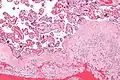

Acute choriodeciduitis, with neutrophils seen in the chorion and decidua.

Gross pathology of fetal membranes versus decidua